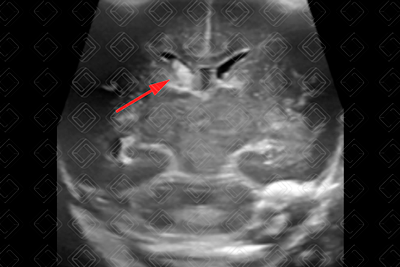

Descrição da figura 6: Ultrassonografia transfontanela; imagem coronal. Presença de foco ecogênico junto do caudado esquerdo (seta vermelha). Após um olhar mais apurado, é possível ver área ecogênica intraparenquimatosa na região temporal esquerda (seta amarela). Independente dos outros achados, a presença de hemorragia intraparenquimatosa já caracteriza a hemorragia de matriz germinal como grau IV.

• Grau IV: Grau I, II ou III com extensão para o parênquima cerebral (figura 6).